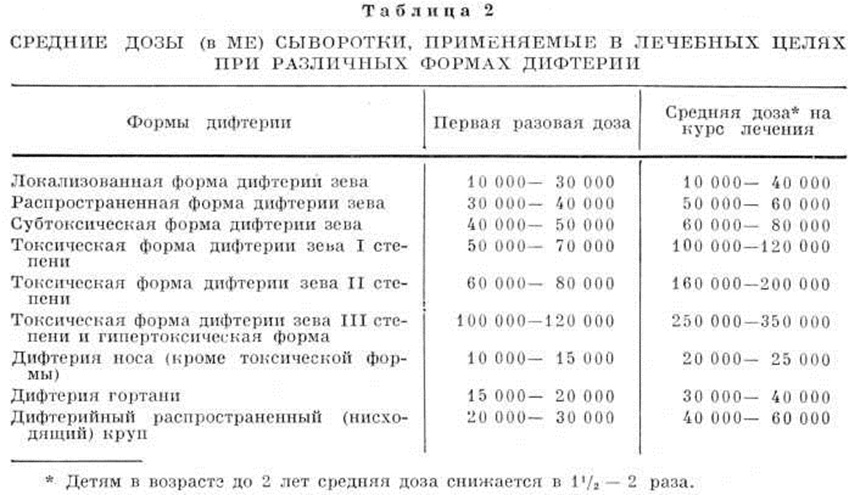

При распространённой форме, крупе во второй и третьей стадиях и особенно при субтоксической и токсической формах необходимо многократное введение сыворотки до значительного уменьшения явлений местного процесса (налётов); сыворотка вводится в дозах, сниженных против начальной вдвое, втрое. Первое введение проводится дробно по модифицированному способу Безредки (смотри полный свод знаний Безредки методы): вначале вводят подкожно 0,1 миллилитров, через 30 минут — 0,2 миллилитров и спустя ещё 1 — 1½ часа всю остальную дозу сыворотки. Доза сыворотки устанавливается исходя из тяжести болезни (клинической, формы) и сроков, истекших с момента заболевания (смотри таблица 2).